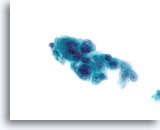

Proliferatieve ductale laesie, Borst FNA, Directe uitstrijk.

Stratificatie van de ductale cellen staat bekend als hyperplasie of proliferatieve veranderingen. Storend bloed en de dikte van de fragmenten maken het moeilijk om in te schatten hoe veel hyperplasie aanwezig is.

Proliferatieve ductale laesie, Borst FNA, Directe uitstrijk.

Stratificatie van de ductale cellen staat bekend als hyperplasie of proliferatieve veranderingen. Storend bloed en de dikte van de fragmenten maken het moeilijk om in te schatten hoe veel hyperplasie aanwezig is.

Proliferatieve ductale laesie, Borst FNA, Directe uitstrijk.

Bij een sterkere vergroting kan men door van boven naar beneden te focussen enkele vermoedelijke myoepitheliale cellen zien die vermengd zijn met de ductale cellen en vermoedelijke spleetachtige ruimten. Deze twee kenmerken zijn kenmerkend voor ductale hyperplasie van het gewone type, een laesie die ruwweg een tweevoudige toename in het relatieve risico van borstkanker vertegenwoordigt.[14].

Proliferatieve ductale laesie, Borst FNA, Directe uitstrijk.

Bij een sterkere vergroting kan men door van boven naar beneden te focussen enkele vermoedelijke myoepitheliale cellen zien die vermengd zijn met de ductale cellen en vermoedelijke spleetachtige ruimten. Deze twee kenmerken zijn kenmerkend voor ductale hyperplasie van het gewone type, een laesie die ruwweg een tweevoudige toename in het relatieve risico van borstkanker vertegenwoordigt.[14].